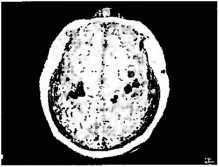

Наш эмоциональный отзыв на зрительный образ является жизненно важным для выживания, но существование связей между зрительными центрами в мозгу и лимбической системой или эмоциональной сердцевиной мозга поднимает также и другие интереснейшие вопросы: что такое искусство; как мозг отзывается на прекрасное? Учитывая, что речь идет о связи между зрением и эмоциями, а искусство предполагает эстетическую эмоциональную реакцию на зрительные образы, такие связи определенно должны существовать, и это будет предметом следующей лекции. Заложены ли эти замысловатые связи мозга уже в геноме эмбриона, или они приобретаются в раннем детстве, когда мы начинаем взаимодействовать с миром? Это обращает нас к пресловутым дебатам о наследственности и среде и является центральным вопросом в моем следующем примере, касающемся фантомных конечностей. Большинство людей знают, что это такое. Пациент с ампутированной рукой, потерявший ее в связи с операцией или в результате несчастного случая, продолжает ощущать присутствие этой руки. Хорошо известен пример лорда Нельсона, который ясно чувствовал фантомную руку спустя много времени после ее потери в бою. (Он действительно использовал этот факт как упущенное доказательство существования «нетелесной» души. Ведь если рука способна сохраняться при физическом устранении, почему этого не может делать все тело? — спрашивал он.) Однажды я работал с пациентом, которому ампутировали руку выше левого локтя. Он сидел в моем кабинете с закрытыми глазами, пока я осторожно касался разных частей его тела и просил его говорить, каких именно. Все шло нормально, пока я не прикоснулся к его левой щеке, в этот момент он воскликнул: «О боже, вы дотронулись до большого пальца моей левой руки!» (иными словами, его фантомного пальца). Он был удивлен не меньше моего. Касание верхней губы вызвало ощущение в его фантомном указательном пальце, а подбородка — в его фантомном мизинце. Это была полная, систематическая карта его утраченной руки, нанесенная на лице (см. рис. 1.4). Почему это происходит? Загадка фантомных конечностей, как и синдром Капгра, могли бы заинтриговать Шерлока Холмса. Что же, в конце концов, происходит? И снова ответ надо искать в анатомическом строении мозга. Тактильные сигналы от поверхности кожи левой стороны туловища проецируются в правом полушарии, на вертикальный участок корковой ткани, называемый постцентральной извилиной. На самом деле существует несколько таких карт, но для простоты мы предположим, что есть только одна, и назовем ее S1 — на постцентральной извилине. Это достоверное «представительство» всей поверхности тела — как если бы там находился маленький человечек, прислонившийся к этой поверхности мозга (см. рис. 1.5) Мы называем его гомункулусом Пенфилда, и для большинства частей тела он неизменен — чему, собственно, и должна соответствовать карта. И все‑таки здесь есть одна странность: проекция лица на карте поверхности мозга находится непосредственно сразу вслед за рукой, а не рядом с шеей, как можно было бы ожидать. Голова оказывается вывихнутой (почему это происходит — неясно, возможно, это как‑то связано с филогенезом [22] или способом развития мозга на эмбриональной или младенческой стадии). Это дало мне ключ к тому, что произошло. Когда рука была ампутирована, больше ни один сигнал не был получен той частью коры головного мозга, которая относится к руке. Она стала испытывать голод по сенсорной информации, и в результате сенсорные данные, идущие от кожи лица, стали заполнять примыкающую вакантную территорию, относившуюся к утраченной руке. Затем сигналы от лица стали ошибочно восприниматься более высокими центрами мозга, исходящими от потерянной руки [2] . Специфичность этих сигналов настолько велика, что кубик льда или теплая вода, приложенные к лицу, вызывают такие же ощущения холода или тепла в фантомной конечности. Когда по лицу пациента Виктора текла вода, он также чувствовал, как вода стекает по его фантомной руке. Когда он поднимал свою больную руку вверх, то был поражен, почувствовав струйки воды, которые вопреки законам физики «стекали» вверх по ее фантомной части. ![]() Рисунок 1.4 Указывает на та поверхности тела, которые вызвали ощущения в фантомной руке (эта левая рука пациента была ампутирована за 10 лет до нашего опыта). Обратите внимание на полную карту всех пальцев руки (обозначенных цифрами от 1 до 5) на лице, вторая карта находится на плече. Сенсорный сигнал от этих двух участков кожи, по-видимому, активирует территорию рухи в мозгу (в таламусе или коре). Таким образом, прикосновение к этим участкам вызывает также ощущение от утраченной руки ![]() Рисунок 1.5 а. Проекция поверхности тела на человеческий мозг за центральной бороздой. Гомункулус (карлик) расположен вверх ногами, а его ноги помещаются на срединной (внутренней) поверхности теменной доли ближе к верху, при этом его лицо находится ближе к низу наружной поверхности. Обратите внимание также на то, что лицевая область — ниже области руки в отличие от их реального расположения (рядом с шеей), а гениталии представлены под ногами б. Причудливая трехмерная модель гомункулуса Пенфилда — это человечек в мозгу ![]() Рисунок 1.6 Магнитоэнцефалография (МЭГ): образ экспонируется на магнитно-резонансное отображение мозга пациента, у которого была ампутирована правая рука выше локтя. Мозг рассматривается сверху. Правое полушарие показывает нормальную активацию корковых областей правой рухи (закрашено), лица (черная зона) и плеча (белая зона) в соответствии с картой Пенфилда. В левом полушарии нет активации, относящейся к правой отсутствующей рука, но теперь на згу область распространяется активность, идущая от лица и плеча Чтобы напрямую проверить наши гипотезы «преобразования карты» и «перекреста проводов», мы использовали технику магнитоэнцефалографии, или МЭГ. Она показывает, какая часть мозга активируется при тактильном раздражении различных частей тела. Достаточно достоверно мы обнаружили, что у Виктора да и других пациентов с ампутированными конечностями) касание лица активирует не только область лица в мозгу, но также район руки в соответствии с картой Пенфилда (см. рис. 1.6). Это сильно отличается от картины, которую можно видеть у здорового мозга, — в данном случае касание лица активирует только лицевую область коры. |